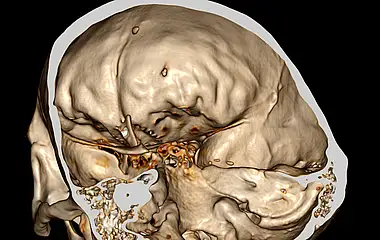

Die komplexe Anatomie und Nähe zu lebenswichtigen Strukturen sowie den wichtigen Steuerungszentralen der Hormone machen Erkrankungen der Schädelbasis stellen besondere Anforderungen an Diagnostik und Therapie. Als Teil des interdisziplinären zertifizierten Schädelbasiszentrums am Uniklinikum Augsburg besitzt die Klinik für Neurochirurgie eine große Expertise im gesamten Spektrum der operativen Therapie an der Schädelbasis. Dazu gehören Schädelbasistumoren wie Meningeome, Schwannome (Vestibularisschwannome), Hypophysentumore, Vaskuläre Dekompression bei Gefäß-Nervenkonflikten (Trigeminusneuralgie) sowie die Versorgung komplexer Schädelbasisfrakturen.

Seltenere Tumore sind Kraniopharyngeome, Chordome, Chondrosarkome, Metastasen oder Gefäßmalformationen. Zudem können Tumor aus dem Nasen- und Mittelgesichtsbereich die Schädelbasis infiltrieren (z.B. Karzinome, Ästhesioneuroblastome)

Die Behandlung von Pathologien erfordert Erfahrung, Präzision, interdisziplinäre Zusammenarbeit mit den Kliniken für Hals-Nasen-Ohrenheilkunde, Neuroradiologie, Endokrinologie und Strahlentherapie. Oberstes Ziel ist die Sicherheit der Patientinnen und Patienten. Dazu gehört auch zu wissen, wann man nicht weiter gehen kann. Wir nutzen die neueste Technik um diese Ziele zu erreichen. So führen wir unsere Operationen mikrochirurgisch oder unter Zuhilfenahme eines Endoskops durch. Die Planung erfolgt bereits vor der Operation und kann mittels Neuronavigation wie geplant durchgeführt werden. Zur Schonung der Nerven und wichtiger Strukturen setzen wir routinemäßig das intraoperative Neuromonitoring ein um in Echtzeit während der Operation drohende Schädigungen zu erkennen und zu vermeiden.